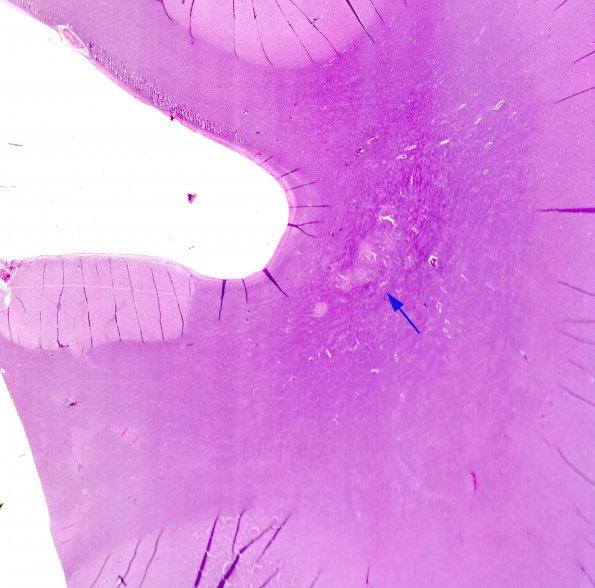

Closeup of deep white matter adjacent to the ventricular surface demonstrates scattered nodular heterotopias (arrow), shown at higher magnification in image #1C2.